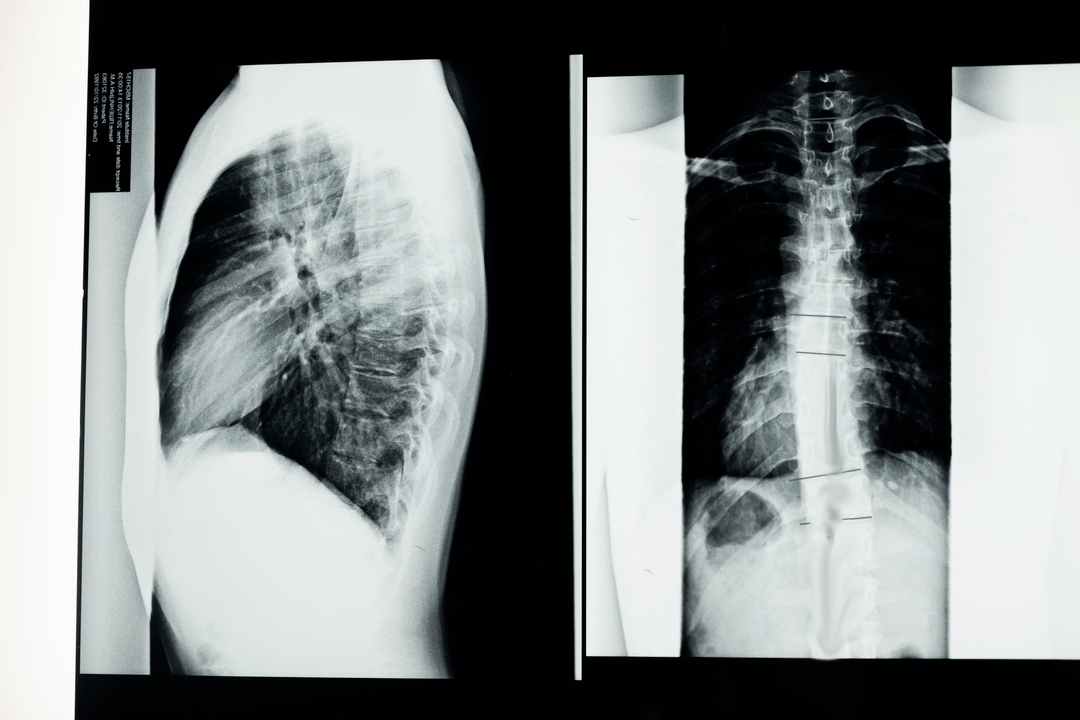

Diagnosis of cervical osteochondrosis

To identify the causes, signs and complications of cervical osteochondrosis, the following studies may be prescribed:

- CT;

- neck radiography in flexion and extension positions;

- MRI.